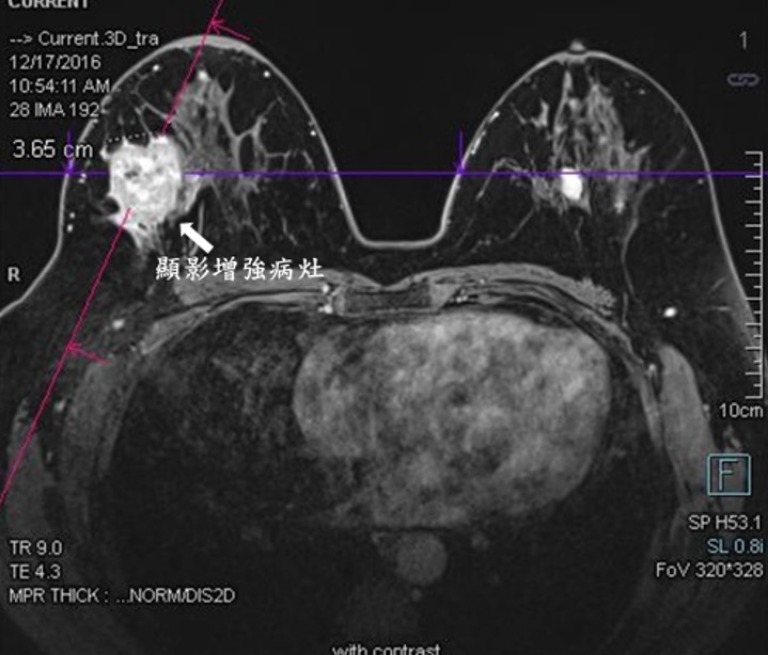

一般對象為40歲以上的年齡層女性;太年輕的女性,由於乳腺比較緻密,顯影成效較差比較不適合利用乳房攝影來偵測早期乳癌;不過要提醒各位女性朋友,乳房X光攝影雖然是乳癌篩檢的有效儀器,但它在診斷乳癌上並非萬無一失,約15%的乳癌在X光攝影是呈現正常影像,臨床上必要時仍要搭配乳房超音波檢查以達相輔相成的效果;雖然過去攝影報告正常但在進行下次乳房X光攝影檢查期間,若乳房發現有以往不曾出現的症狀,多需進一步就醫,以免有所遺漏。另外乳房核磁共振檢查(MRI)則是除了乳房超音波與乳房攝影外較常使用的檢查儀器(圖3)。

MRI臨床常應用於高危險族群的乳癌篩檢,如:家族遺傳型乳癌,帶BRCA1、BRCA2、或TP53基因變異,年輕時胸部接受照射治療者;此檢查選項優點在於有較高機會偵測出以非鈣化點為表現的乳管原位乳癌,而缺點為高敏感性常導致太多不必要的切片手術,因此一般非具有高乳癌風險者或特殊原因考量者不建議以MRI為篩檢選項而是選擇乳房攝影。大多數MRI檢查所發現的腫瘤都有辦法經乳房超音波、乳房攝影看到;除非極小腫瘤才會導致超音波、乳房攝影無法發現。